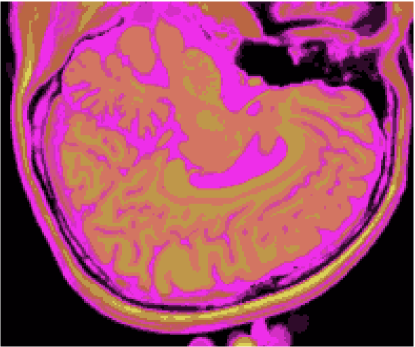

A figura 6 mostra os resultados de classificação, enquanto a figura 7 exibe os resultados de quantização para a imagem sem ruído da fatia 97, figura 5, usando os métodos KO, CM, KM, ODC-PME e ODC-CAN. Esses resultados ilustram qualitativamente as diferenças entre os métodos de classificação e quantização, dado que a fatia 97 possui todas as 13 classes presentes na análise [51].

Figura 6: Composição colorida R0-G1-B2 das imagens da fatia 97 ponderadas em PD, T1subscript𝑇1T_{1} e T2subscript𝑇2T_{2} (a) e resultados de classificação usando os métodos KO (b), CM (c), KM (d), ODC-PME (e) e ODC-CAN (f)

A tabela 2 mostra os resultados da avaliação dos métodos de classificação não supervisionada quanto à quantização vetorial, usando os índices de fidelidade ϵMEsubscriptitalic-ϵME\epsilon_{\textnormal{ME}}, ϵMAEsubscriptitalic-ϵMAE\epsilon_{\textnormal{MAE}}, ϵMSEsubscriptitalic-ϵMSE\epsilon_{\textnormal{MSE}}, ϵRMSEsubscriptitalic-ϵRMSE\epsilon_{\textnormal{RMSE}} e ϵPSNRsubscriptitalic-ϵPSNR\epsilon_{\textnormal{PSNR}}, considerando todas as 181 fatias com 3 bandas (DP, T1subscript𝑇1T_{1} and T2subscript𝑇2T_{2}), para os métodos KO, CM, KM, ODC-PME e ODC-CAN e 0% de ruído. Já os gráficos das figuras 8, 9, 10 e 11 mostram os resultados em função do nível percentual de ruído para os diversos métodos, para um total de 6 volumes de 181 fatias de 3 bandas, totalizando 1086 imagens coloridas, ou 3258 imagens em níveis de cinza.

Figura 7: Composição colorida R0-G1-B2 das imagens da fatia 97 ponderadas em PD, T1subscript𝑇1T_{1} e T2subscript𝑇2T_{2} (a) e resultados de quantização usando os métodos KO (b), CM (c), KM (d), ODC-PME (e) e ODC-CAN (f)